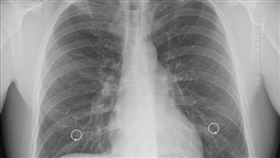

下背痠痛、下肢無力 竟是癌症骨轉移

根據WHO最新統計,女性乳癌已經成為全球最常被診斷出...

2021/03/04 01:10